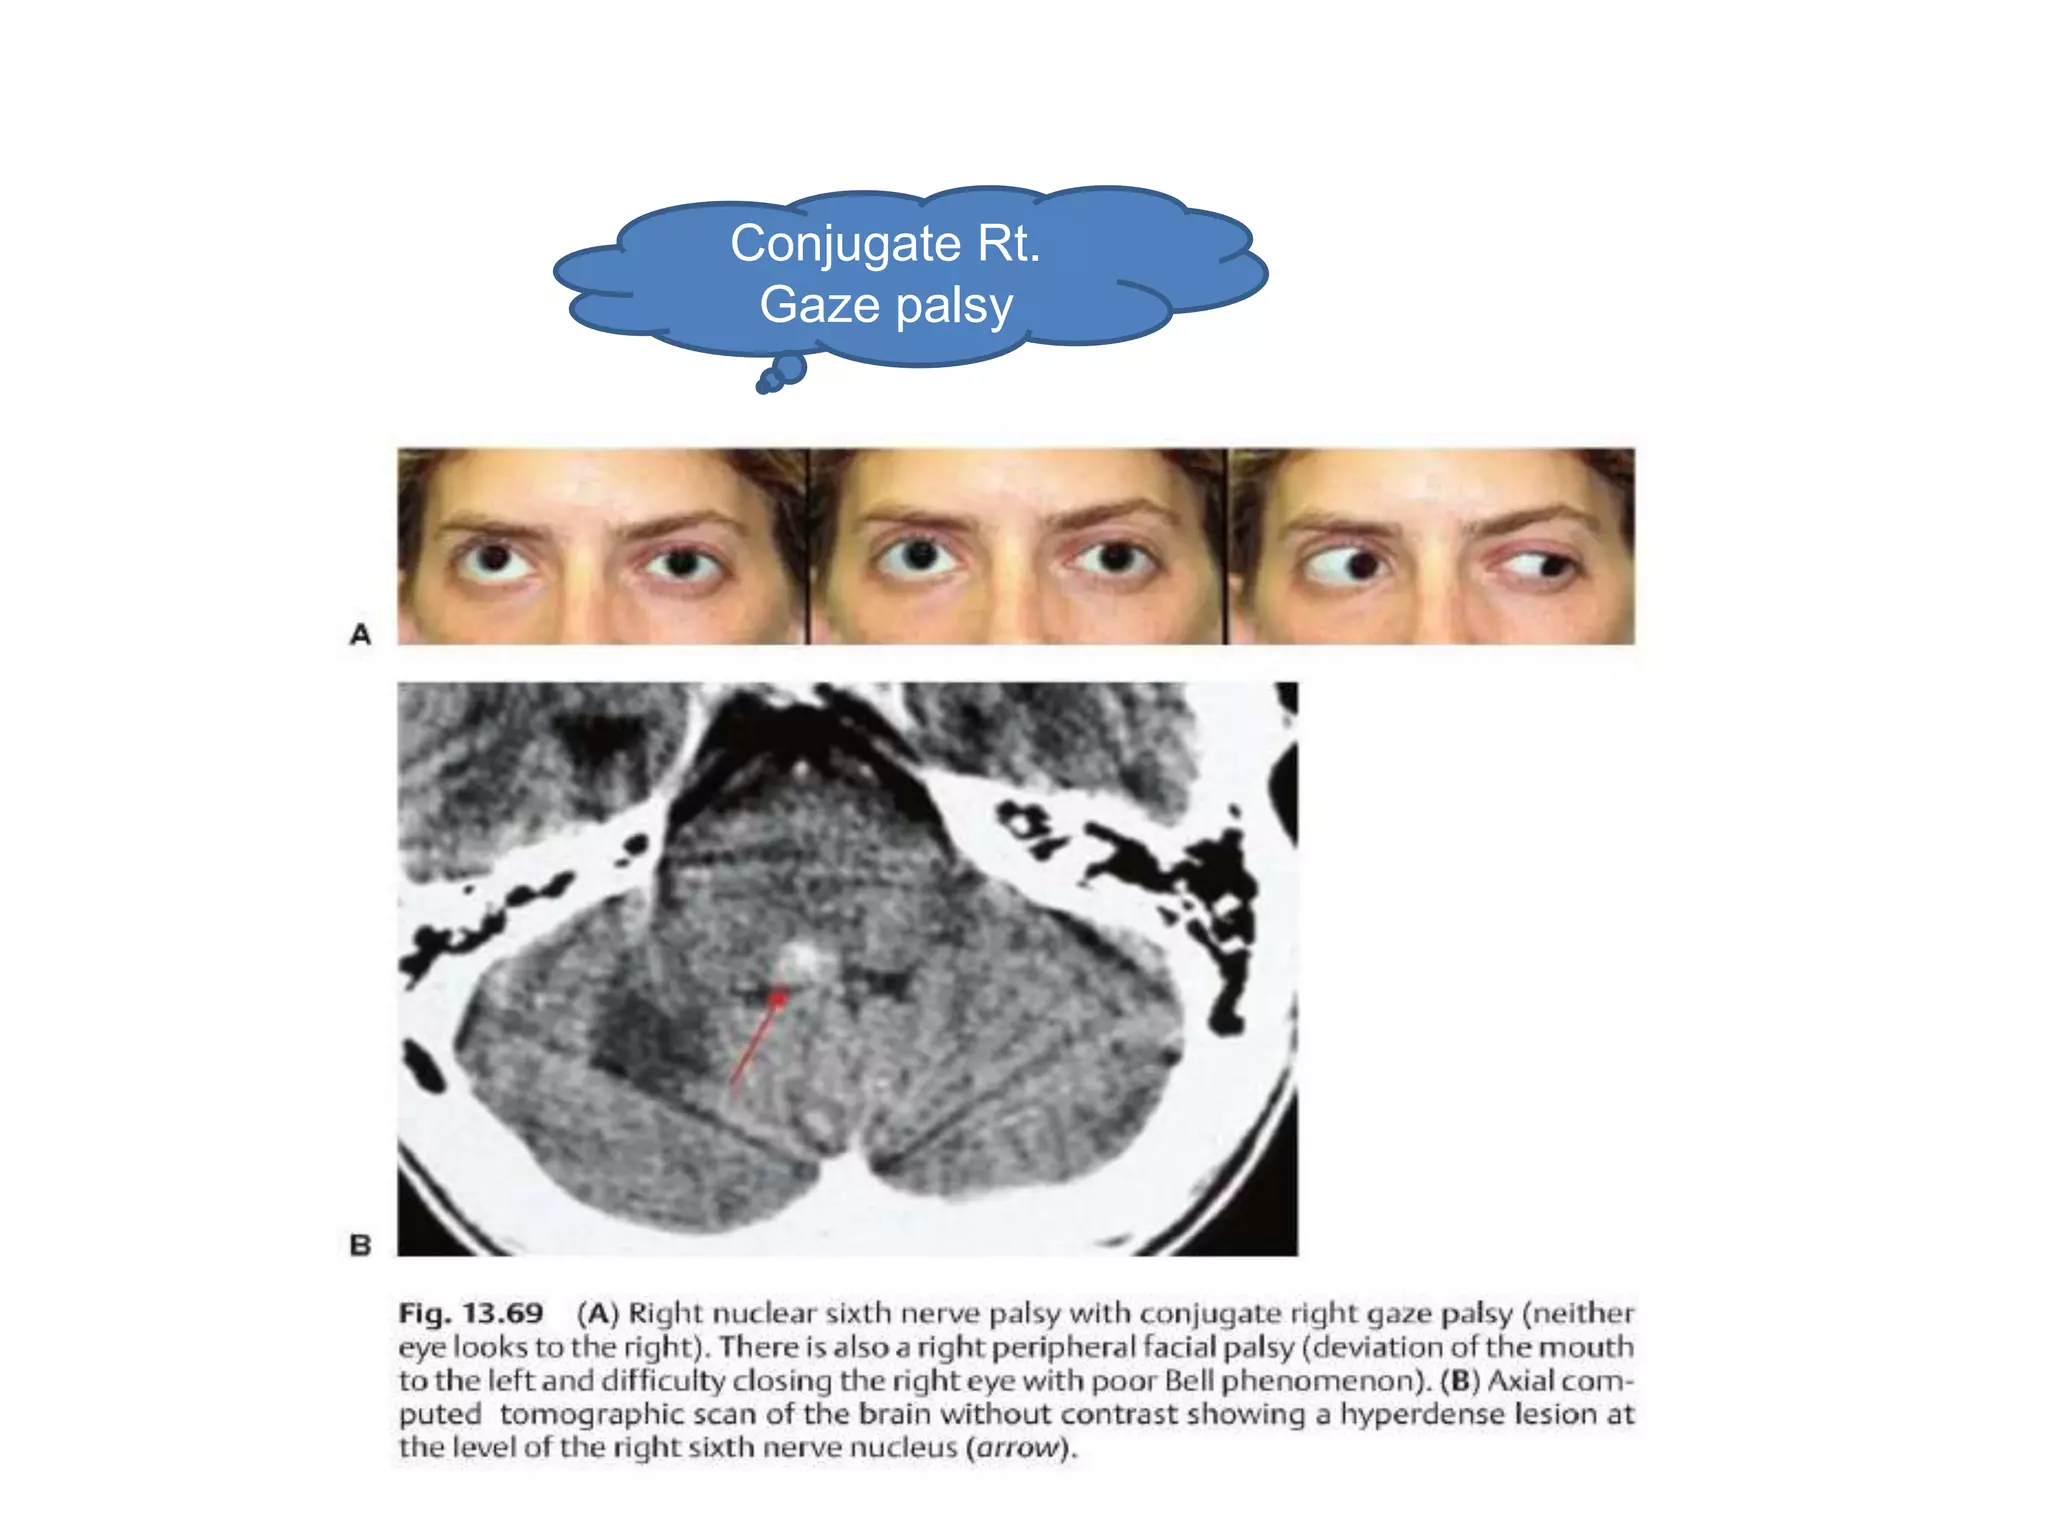

6th n. anatomy

– Nucleus(med. Dorsal pontomedullary jc.)(->contralat. MLF-

>subnucleus of 3rd n.) -> subarachnoid space->cavernous

sinus(lat. of int. caroid a.)->sup. Orbital fissure, annulus of Zinn -

>lat. Rectus m.

Conjugate Rt.

Gaze palsy

Horizontal gaze paresis

• Lesion of 6th n. nucleus

– Loss of ipsilat. Voluntary and reflexive conjugate

movement

– Ipsilat. Facial weakness

6th n. anatomy –Nucleus(med. Dorsal pontomedullary jc.)(->contralat. MLF- >subnucleus of 3rd n.) -> subarachnoid space->cavernous sinus(lat. of int. caroid a.)->sup. Orbital fissure, annulus of Zinn - >lat. Rectus m.

Horizontal gaze paresis •Lesion of 6th n. nucleus – Loss of ipsilat. Voluntary and reflexive conjugate movement – Ipsilat. Facial weakness